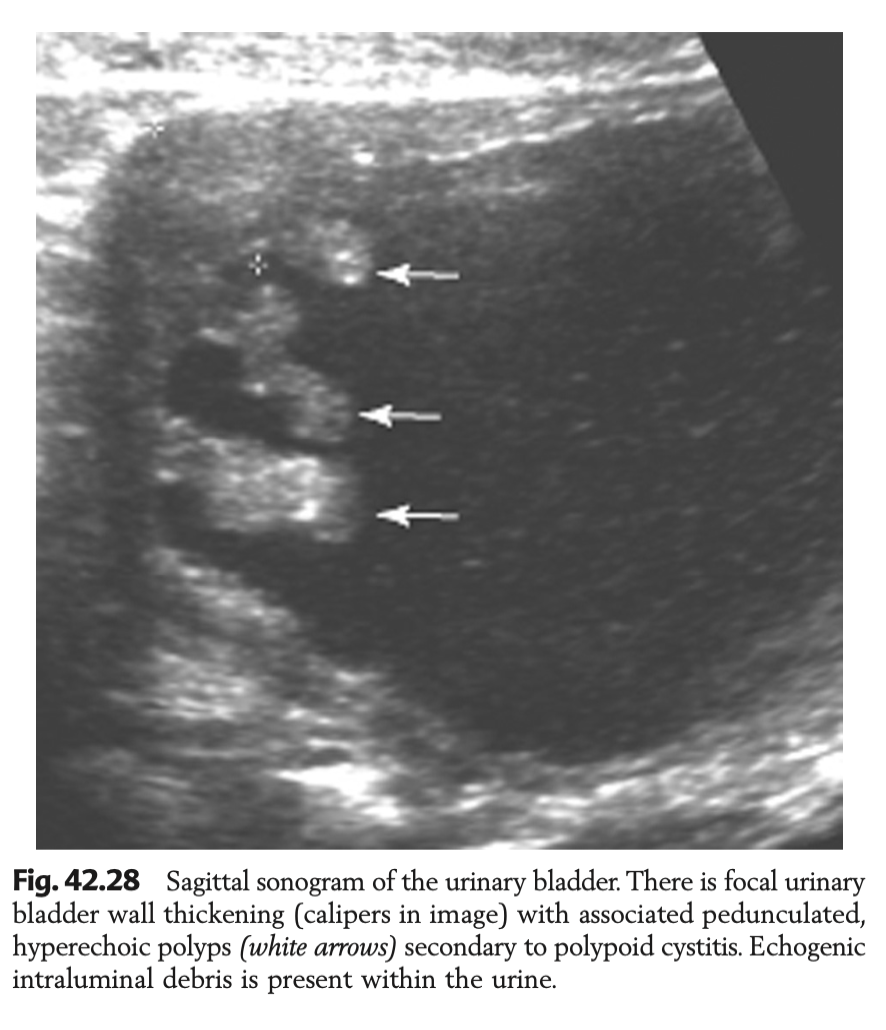

Describe features of US features of polypoid cystitis

Cranioventral OR craniodorsal location

Pedunculated, ovoid or nodular wall changes